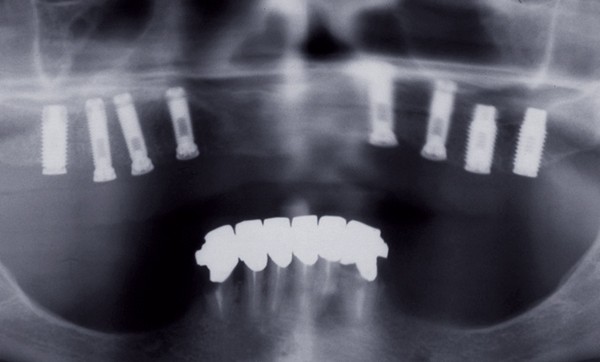

– la création d’espaces entre les implants permettant l’accès à une brosse interdentaire, obligation judicieusement rappelé par Khayat en 2017 [3] (fig. 1) ;

– le positionnement des dents de manière à permettre un soutien efficace de la lèvre supérieure (fig. 2).